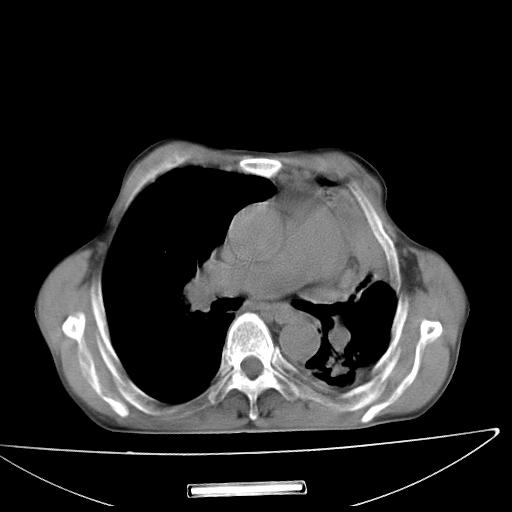

男  70岁,发烧咳嗽4天。盗汗,消瘦。无痰中带血丝,以前有肺tb病史,ct见,双肺tb,左侧胸廓塌陷,左胸膜肥厚粘连。纵隔移位,右侧胸腔积液,大家说说那个心影前左肺舌叶除了肺大炮还有炎症还是干酪性肺炎?有占位吗?我看纵隔淋巴结也大。

1)两肺继发性肺结核并左肺上叶肺不张,支气管扩张。2)双侧胸膜炎(胸膜增厚+少量胸腔积液)。

两肺继发性肺结核并感染,左肺上叶肺不张。建议ct增强。